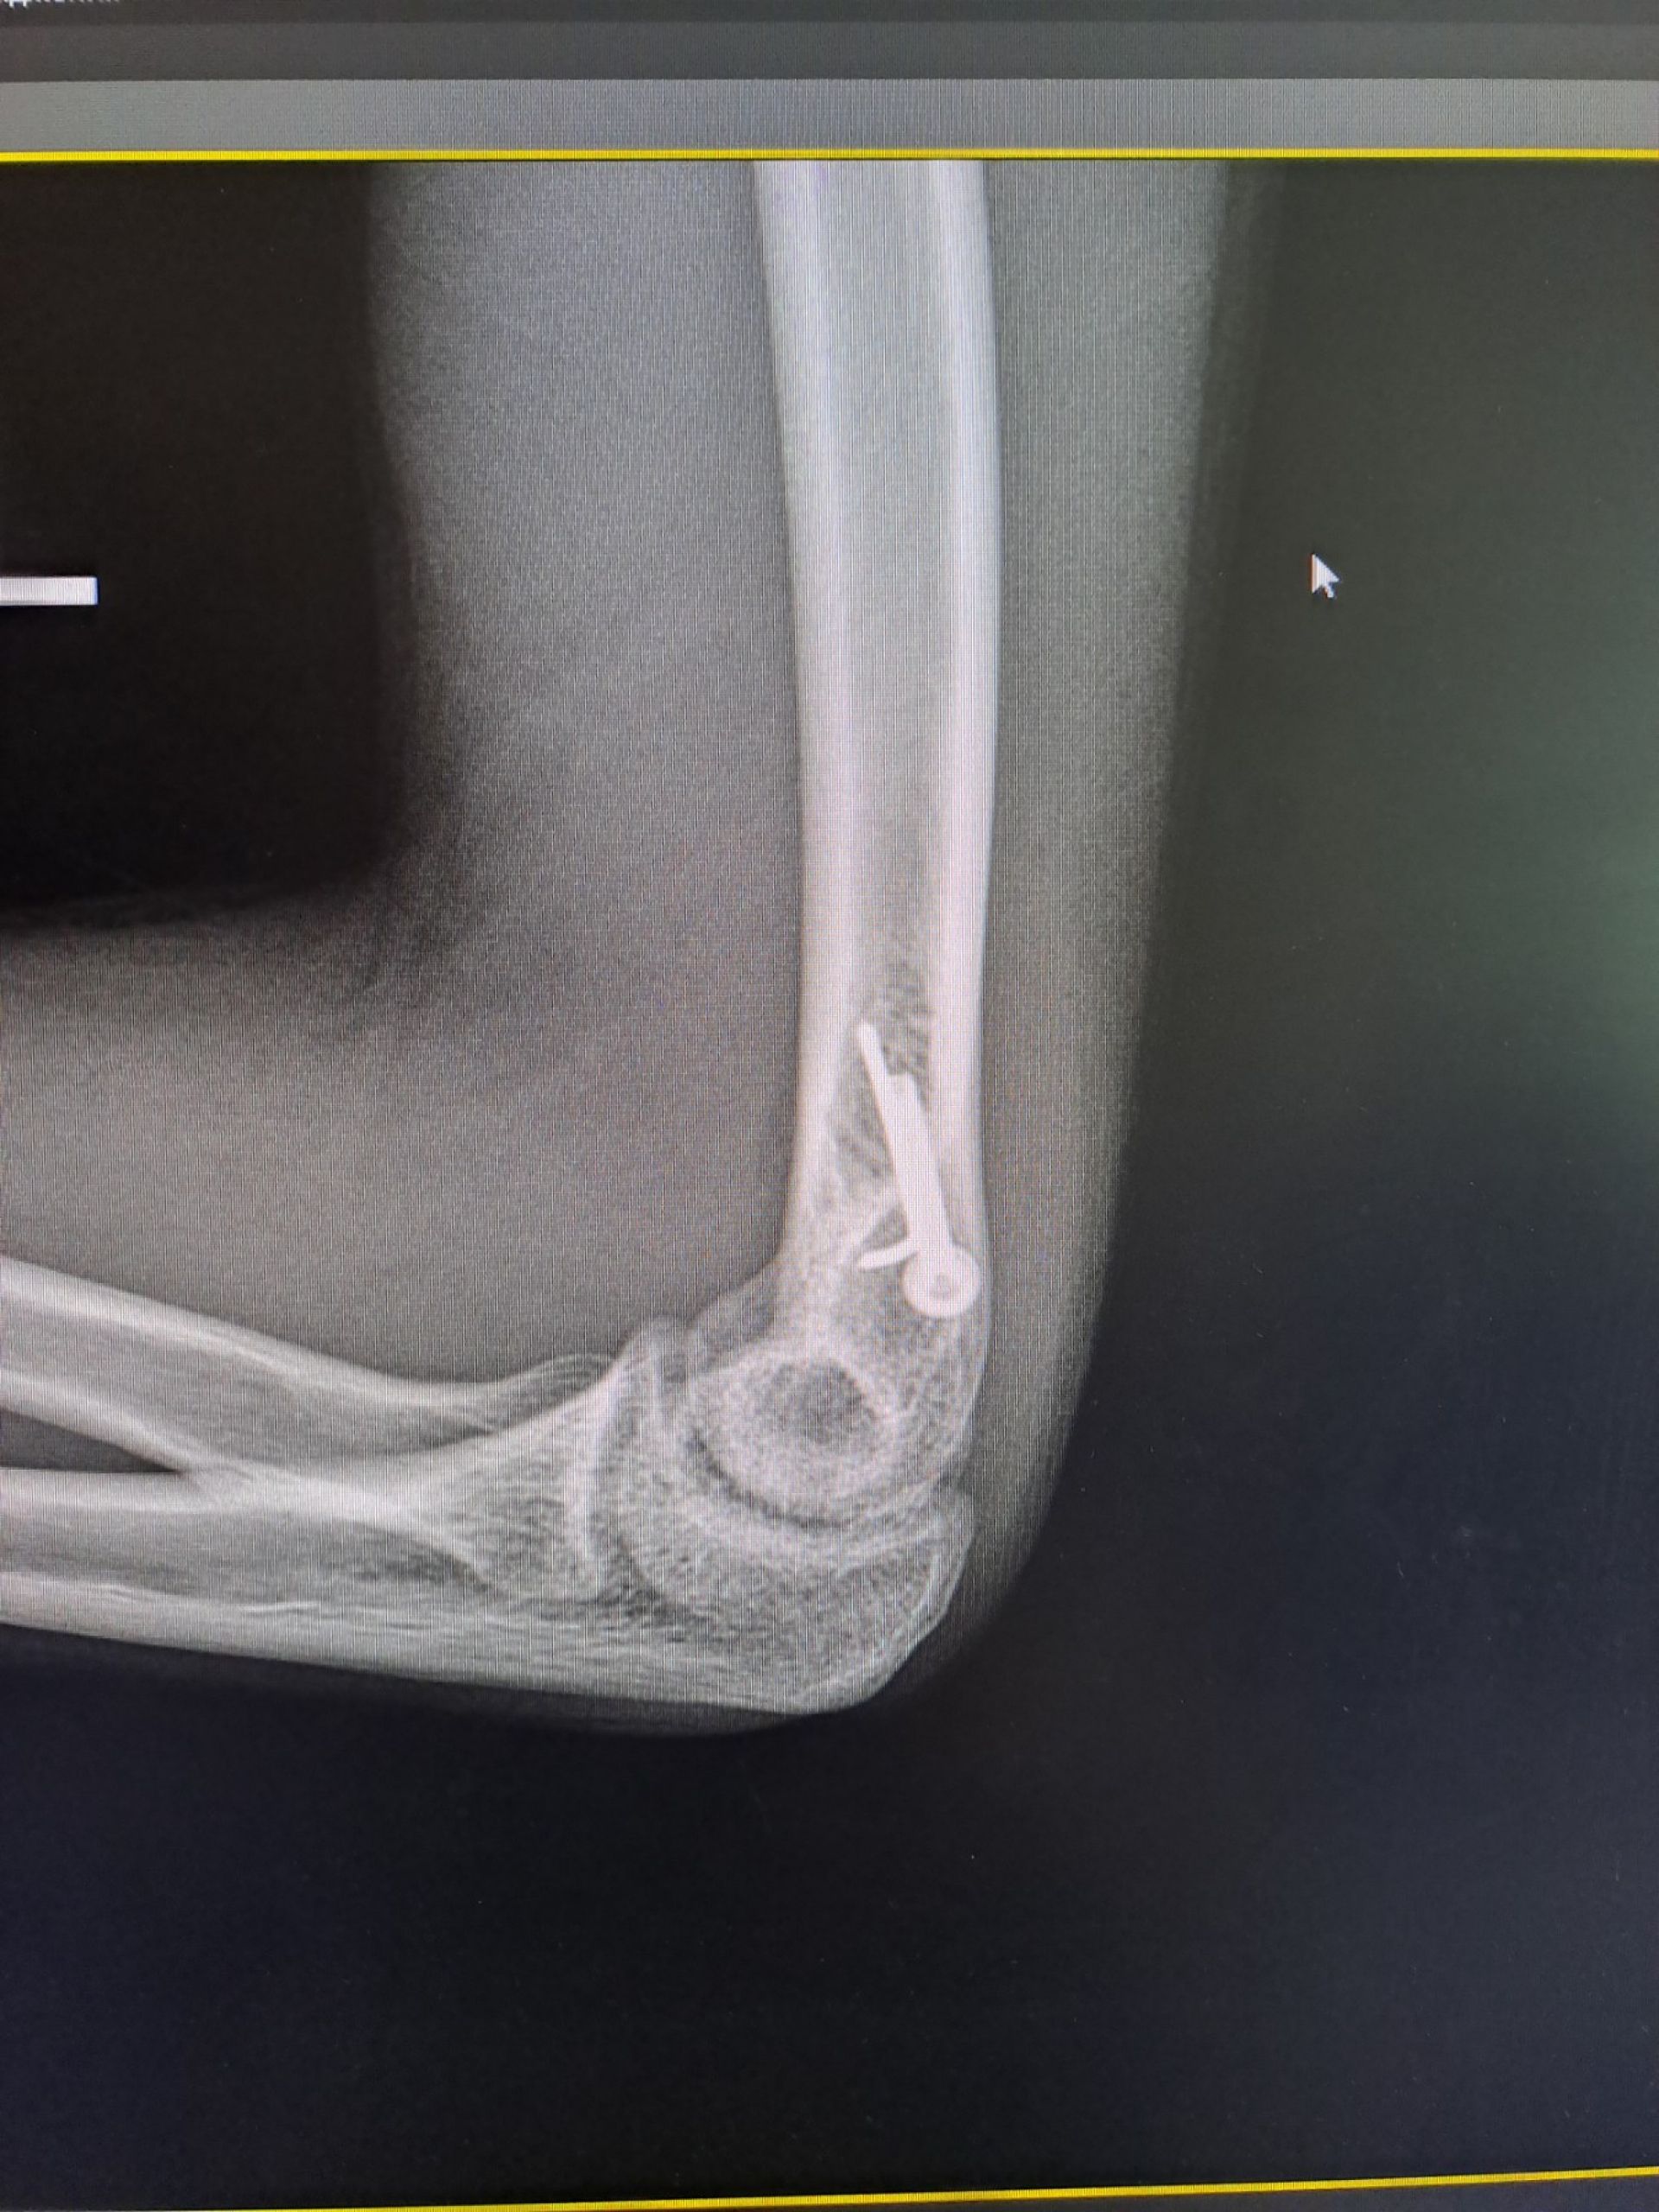

Хлопчик потрапив до травмпункту з вираженим болем та сильною деформацією ліктя. Рентген підтвердив найгірші побоювання медиків: закритий вивих передпліччя разом із переломом плечової кістки. Таке ушкодження вважається нестабільним — це означає, що суглоб буквально «розійшовся», а зв’язки та капсула зазнали значних розривів, передає Вінницька обласна дитяча клінічна лікарня.

- Стабільна фіксація: щоб кістка правильно зрослася, її закріпили спеціальним гвинтом та спицею. Це дозволило не тримати руку в гіпсі занадто довго і почати рухи раніше.